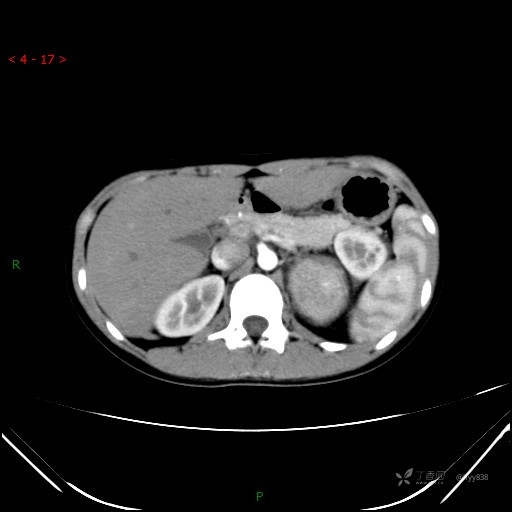

CT值